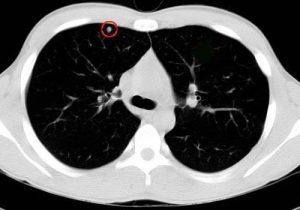

肺结节是一种病因未明的多器官、多系统的肉芽肿性疾病,一般是指在肺内出现圆形或者椭圆形的病灶,直径大多在1到3厘米,多是由于结核钙化灶或者是炎症刺激所引起的局部现象,这种情况建议及时到医院进行检查,可以行病理穿刺,大部分病人会自行缓解;但如果出现恶性结节,需要放疗、化疗、靶向治疗,同时也应该改变生活习惯,戒除不良嗜好。